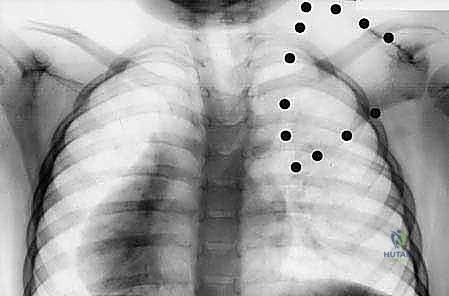

- الأشعة السينية (X-rays): صور شعاعية للكتفين والرقبة والعمود الفقري بأوضاع مختلفة لتقييم موقع لوح الكتف والبحث عن العظم الكتفي الفقري والتشوهات العظمية الأخرى.

- الأشعة المقطعية ثلاثية الأبعاد (3D CT Scan): تعتبر الأداة الأهم في التخطيط الجراحي. توفر صورة مجسمة دقيقة للتشريح العظمي، وتحدد بدقة متناهية حجم وموقع العظم الكتفي الفقري (Omovertebral bone) وعلاقته بالفقرات العنقية، مما يمنع المفاجآت أثناء الجراحة.